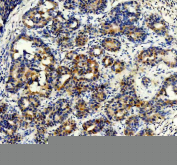

IHC staining of FFPE human thyroid cancer tissue with STXBP4 antibody, HRP-secondary and DAB substrate. HIER: boil tissue sections in pH8 EDTA for 20 min and allow to cool before testing.